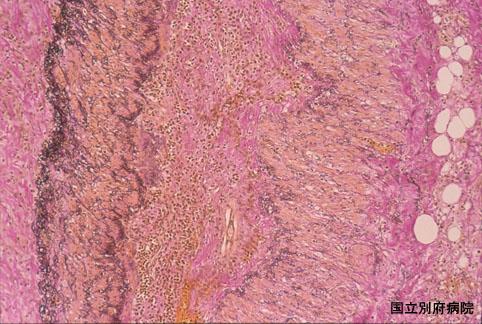

难以鉴别于大肠癌的伴有嗜酸细胞增多症的缺血性大肠炎(病例提供: 国立别府病院)

炎症性・溃疡性疾患/缺血性大肠炎

部位(按器官分)

大肠/升结肠

病理切片(微观)